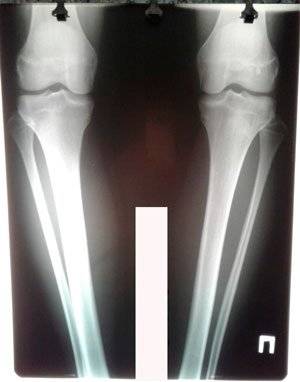

Исходник - 14 лет.

Дата операции - 20.03.2020

Дата снятия аппаратов - 11.06.2020

Срок сращения - 83 дня.